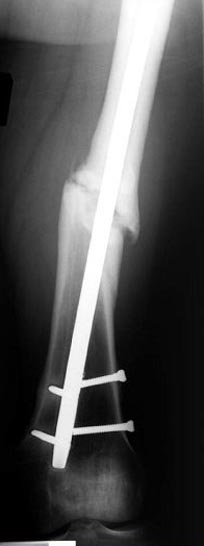

Снимки представлены: 1 мес; 3 мес; 1 год; 2 года, предоперационные и ротационная КТ грамма

Деформация:

Вальгус- 17 градусов

Рекурватум 5 градусов

Укорочение 2.5см

Ротационно 22 градусов внутренная

Смещение диафиза по поперечнику 75%

Операцию провели в два этапа, сперва удалили штифт, рассверливание римером на пару мм большего диаметра, определение чувствительности на анаэробную и аэробную культуру (где исследования показали негативный результат чувствительности), через дней десять - начали аппаратную фиксацию.